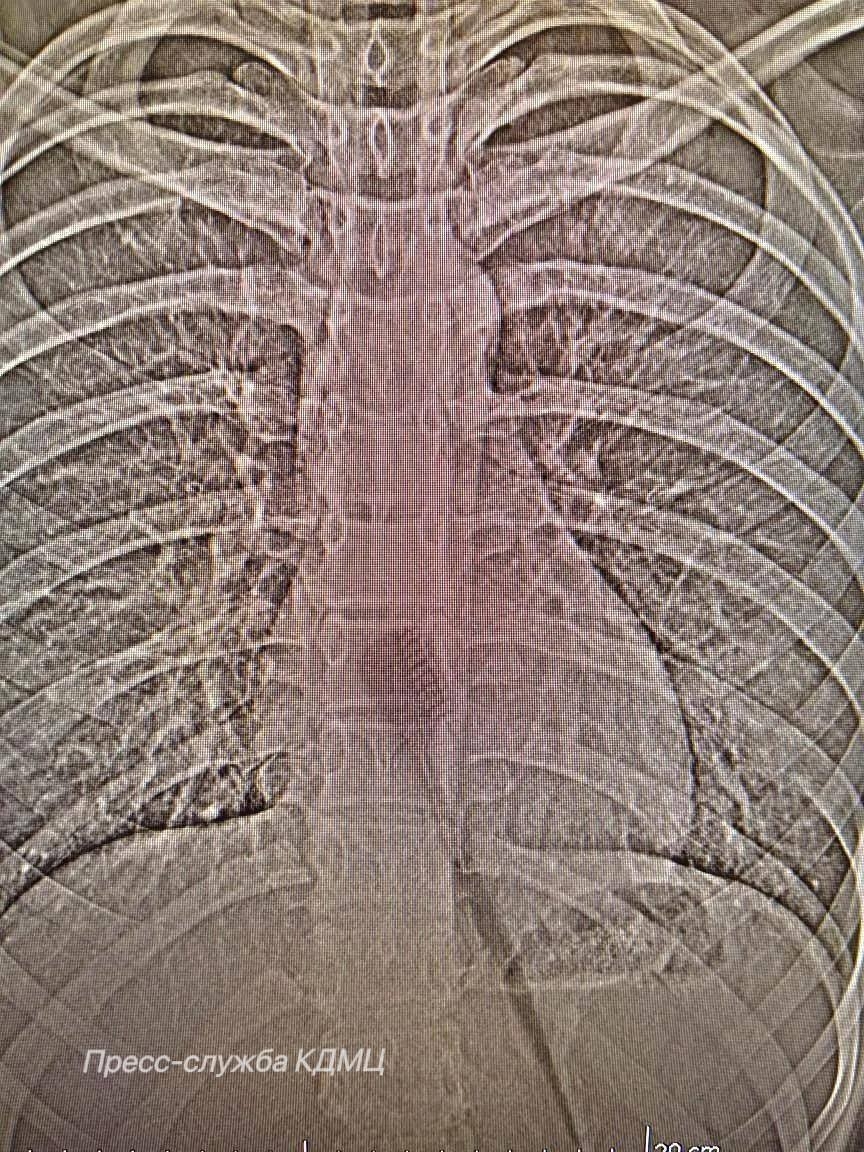

В КДМЦ помогли 13-летней пациентке, которая случайно проглотила зубную щётку длиной 19 см во время чистки зубов. Инородный предмет находился в желудке и частично в пищеводе, что создавало серьёзный риск для здоровья.

Врачи провели малотравматичную эндоскопическую операцию и аккуратно извлекли щётку без разрезов. Девочка быстро восстановилась и уже выписана домой.